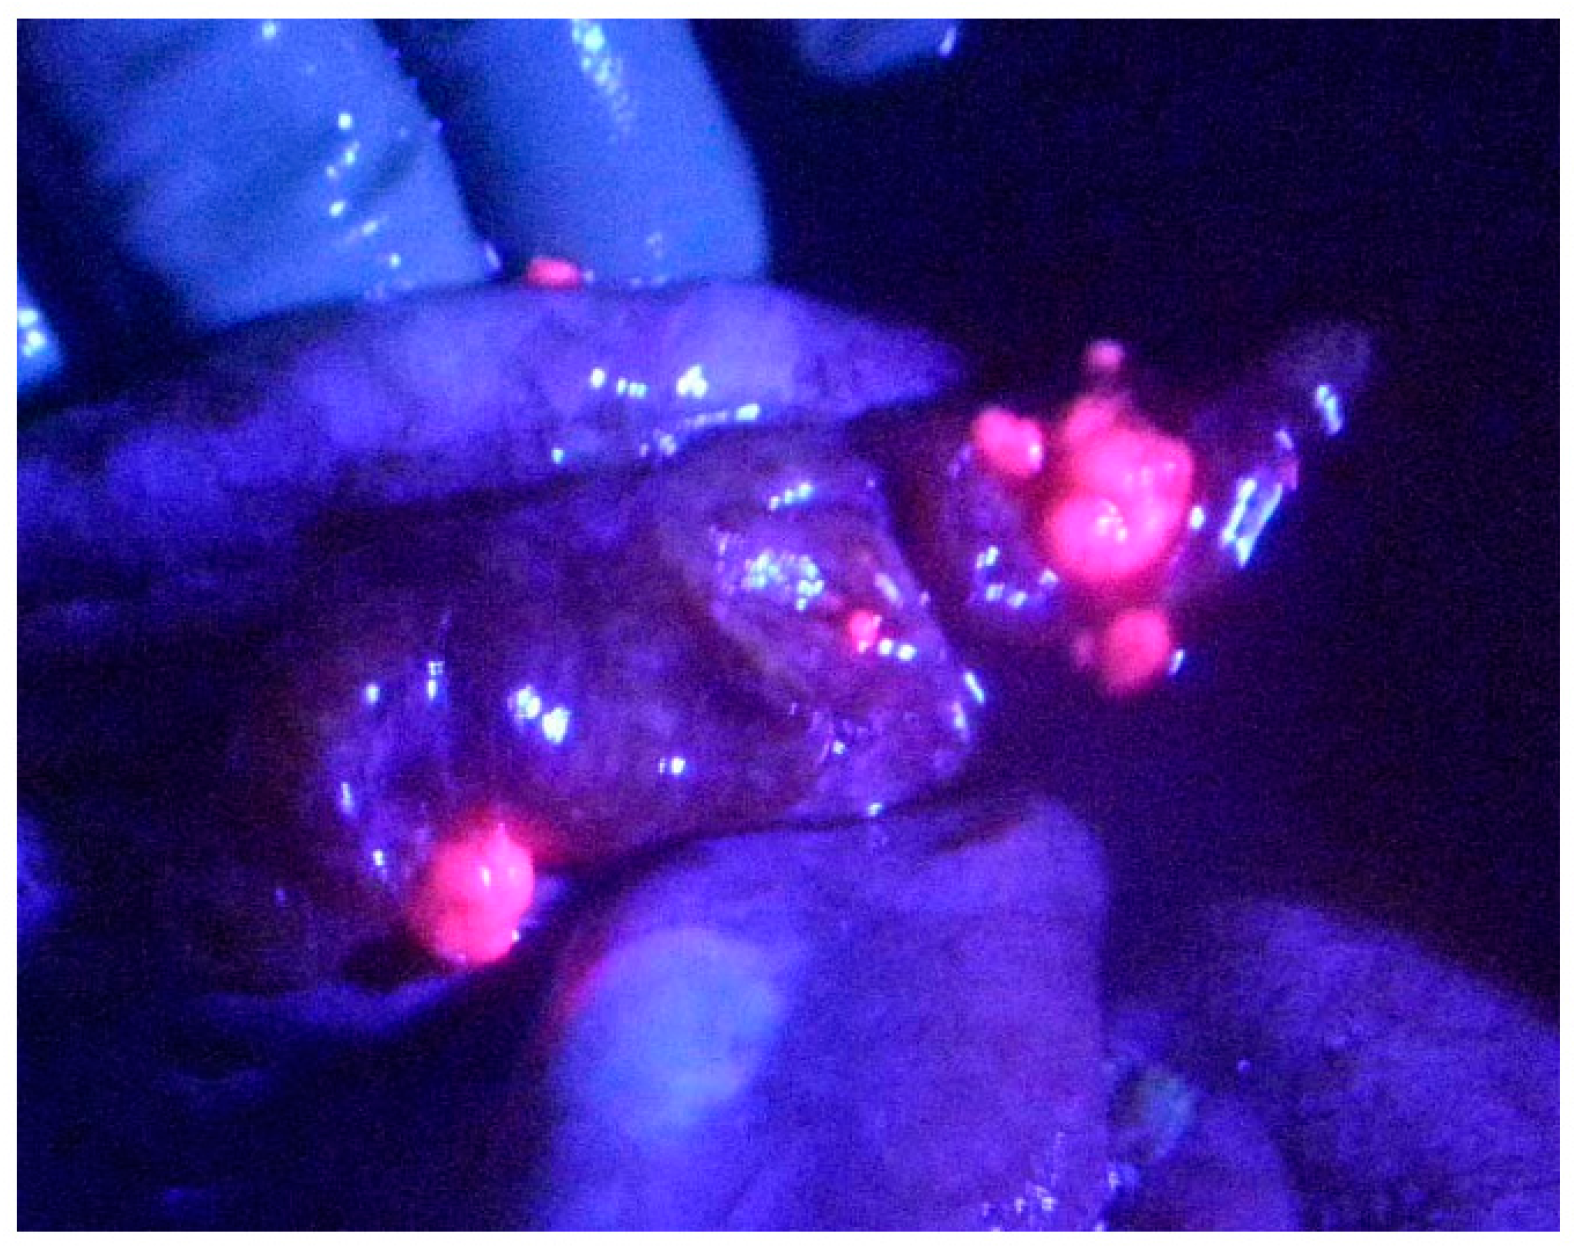

3.2. ALA PDD in Experimental PM

4. Clinical Application of ALA PDD to Detect Peritoneal Metastasis: ALA-Guided Cytoreductive Surgery

4.1. Methods of ALA PDD and ALA-Guided Cytoreductive Surgery

4.2. Results of ALA PDD for Detection of Peritoneal Metastases from Various Cancers